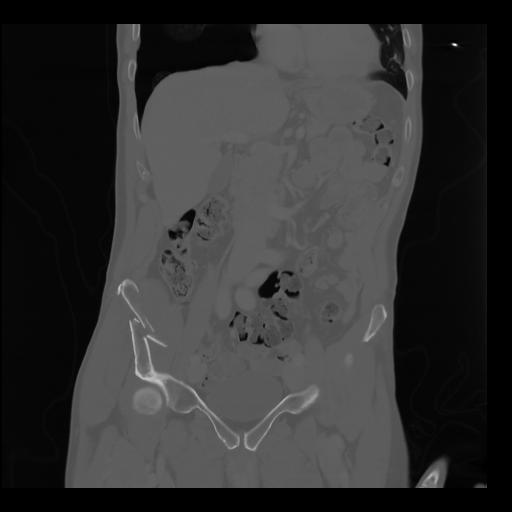

35 CUERPO,CE,Coronal,3.000,CUERPO,Coronal,